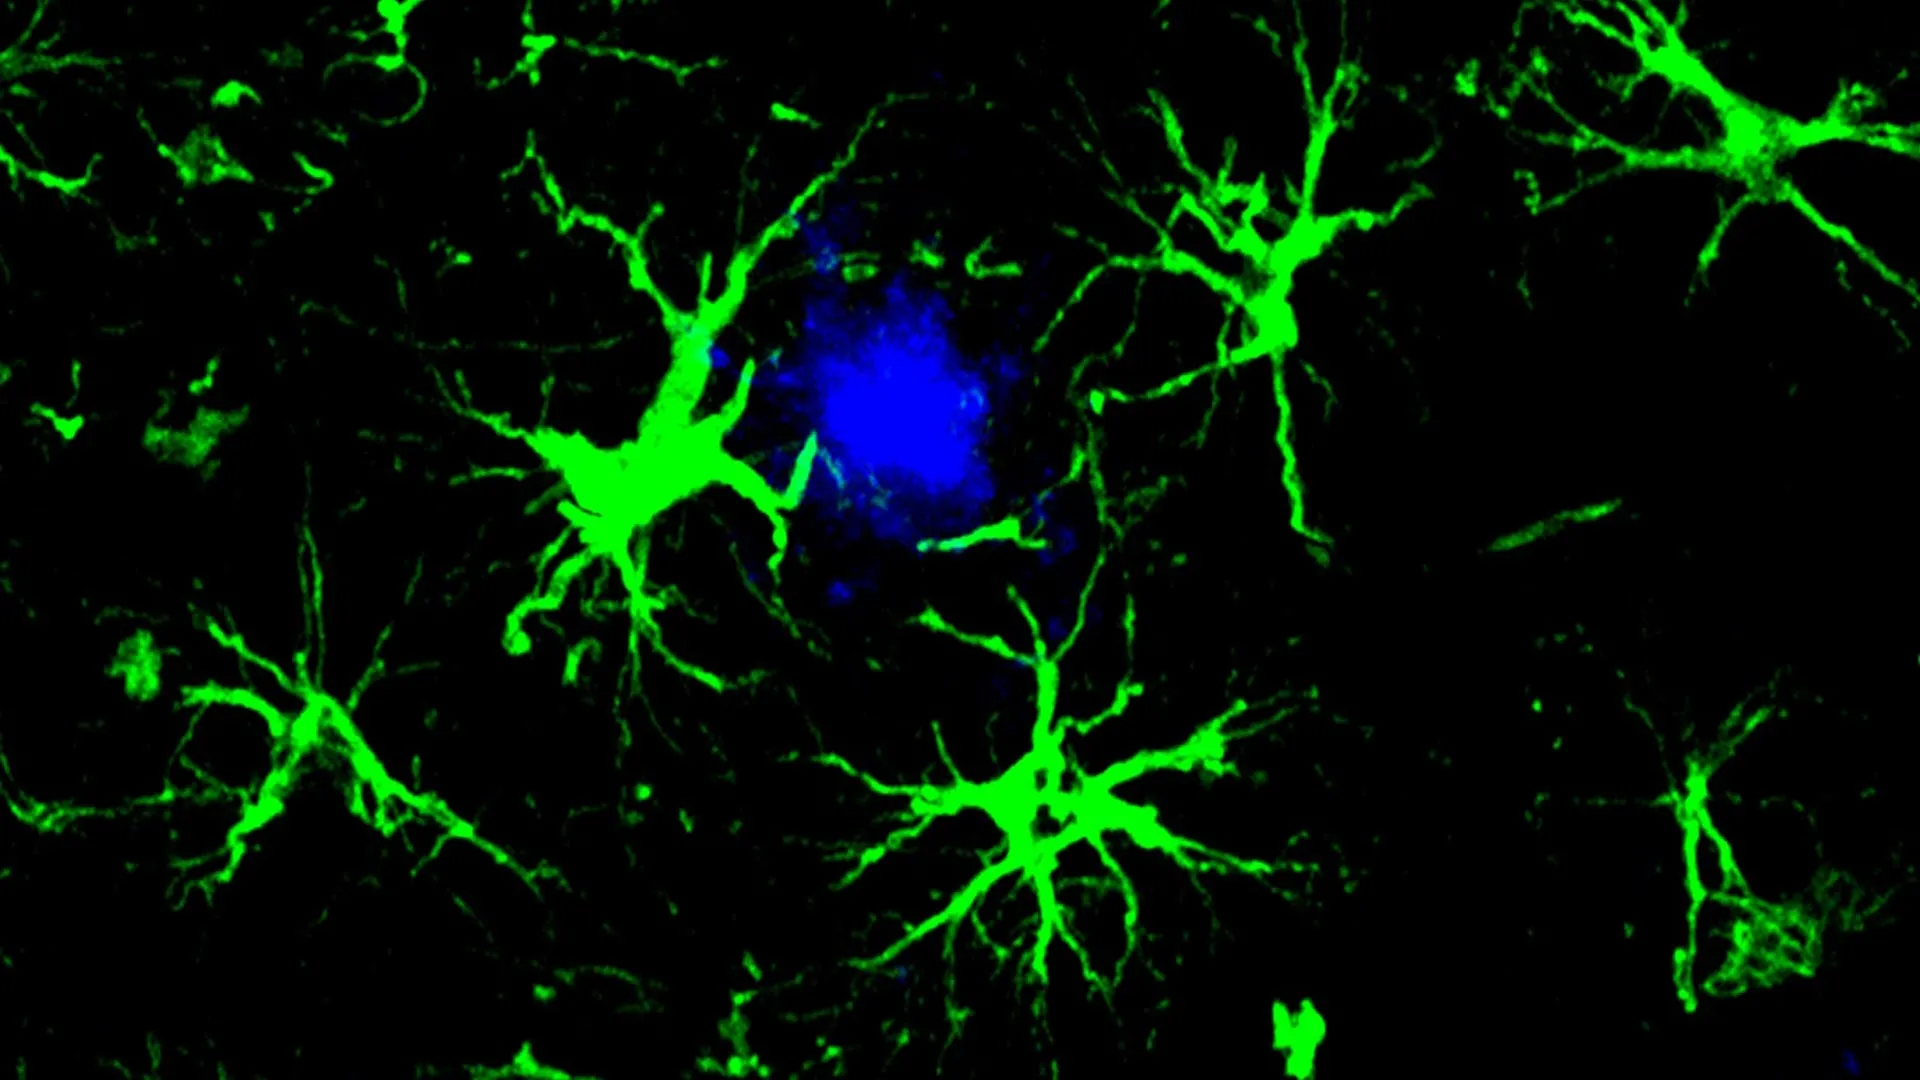

This pioneering strategy draws inspiration from the highly successful chimeric antigen receptor (CAR)-T cell therapies, a cornerstone of modern cancer treatment where a patient’s own T cells are genetically modified to recognize and eliminate malignant cells. In this Alzheimer’s context, however, the focus shifts to a different cellular linage: astrocytes. These ubiquitous glial cells, typically responsible for maintaining the brain’s delicate environment and supporting neuronal function, have been genetically engineered by scientists to incorporate a CAR homing mechanism. This modification equips the astrocytes with the capability to specifically identify and bind to amyloid proteins, subsequently facilitating their removal. These reprogrammed CAR-astrocytes effectively transform into potent cellular agents designed to actively scour the brain for and dismantle the harmful protein aggregates implicated in cognitive decline.

To alleviate the strain on compromised microglia and introduce a novel clearance mechanism, the study’s first author, Yun Chen, PhD, then a graduate student in the laboratories of Dr. Colonna and David M. Holtzman, MD, the Barbara Burton and Reuben M. Morriss III Distinguished Professor of Neurology at WashU Medicine, turned his attention to astrocytes. Recognizing astrocytes as the most abundant cell type in the brain, providing essential support to neurons, Dr. Chen embarked on redesigning them into specialized amyloid-clearing entities. Through the introduction of a gene encoding a chimeric antigen receptor (CAR) via a non-pathogenic viral vector delivered to the mice, these astrocytes were endowed with the capacity to recognize and engulf amyloid beta proteins. This enhanced functionality allows the engineered astrocytes to preferentially target and remove amyloid beta plaques, a crucial intervention for mice genetically predisposed to developing these pathological hallmarks.

In the younger cohort of mice, the administration of the engineered CAR-astrocytes proved instrumental in preventing the formation of amyloid plaques altogether. By the age of approximately six months, a stage where untreated control mice typically exhibit brains densely packed with amyloid plaques, the treated mice showed no detectable signs of these pathological aggregates. For the older cohort, which already presented with substantial plaque burdens at the commencement of treatment, the CAR-astrocyte therapy resulted in a significant reduction of amyloid plaque levels, approximately halving the burden compared to a control group that received a viral vector lacking the CAR gene.